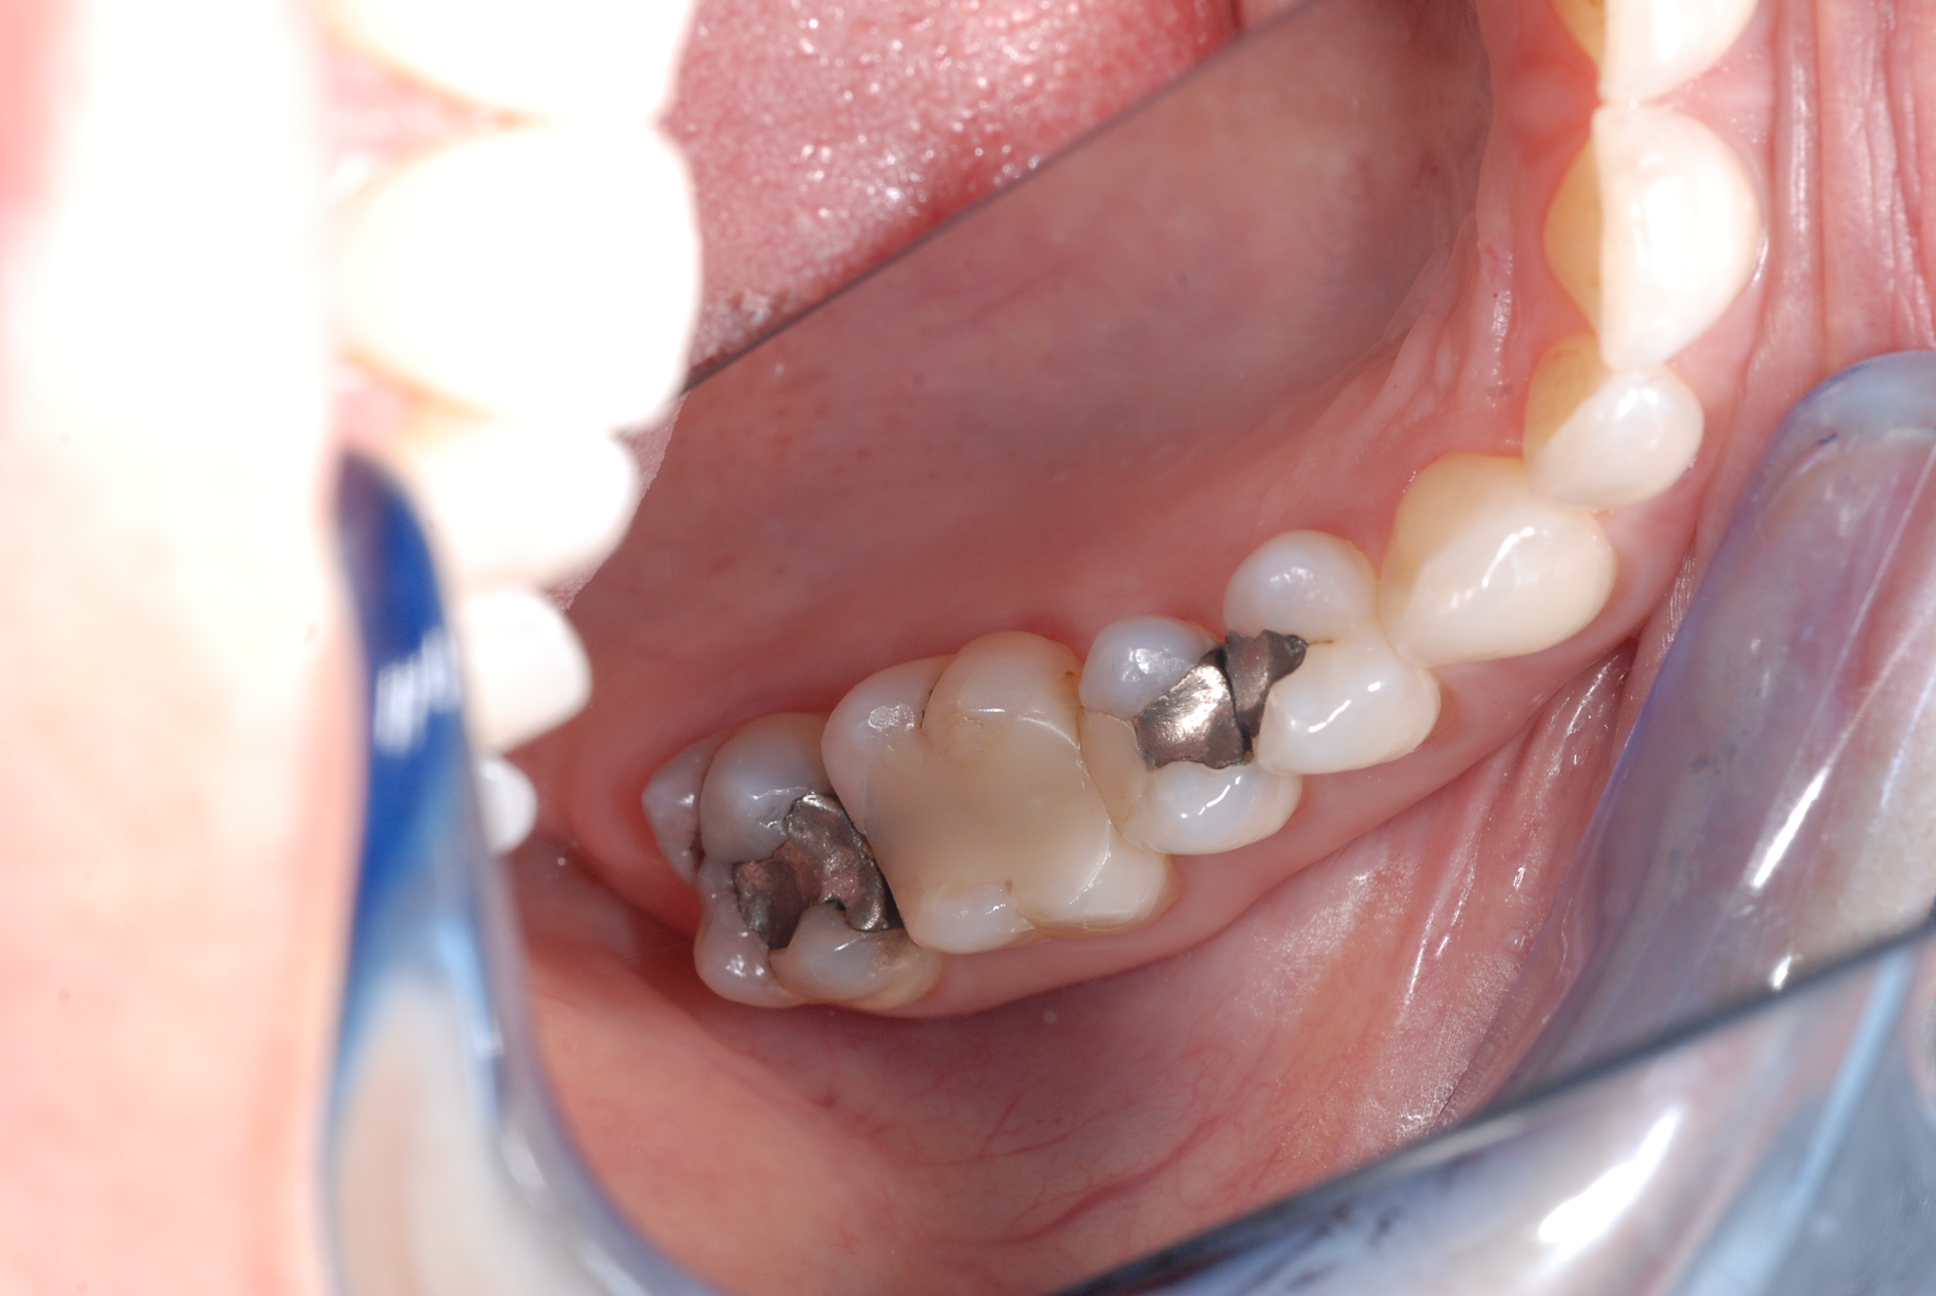

Silver amalgam ( dental amalgam ) has been filled into patient’s teeth for a hundred years, and no one seems to have worried that these fillings corrode like any metal in a moist and tough environment. Corrosion products cause ‘rust like material’ to be absorbed into the inner structures of the tooth and if left untreated, cracks develop in the base of the cavity causing pain and sensitivity. ‘Cracked tooth syndrome’ is a vexing problem of cracked teeth. A beautiful smile begins to age, look gray and lifeless.

At Caring 4 Smiles we brighten patient’s smiles and reduce the risk of cracked teeth by removing amalgam fillings and replacing them with beautiful white bonded composite fillings. Larger fillings are replaced with porcelain crowns or inlays made using the latest CEREC CAD-CAM technology. We fit ‘crowns in a day’ with CEREC technology. It’s truly amazing.